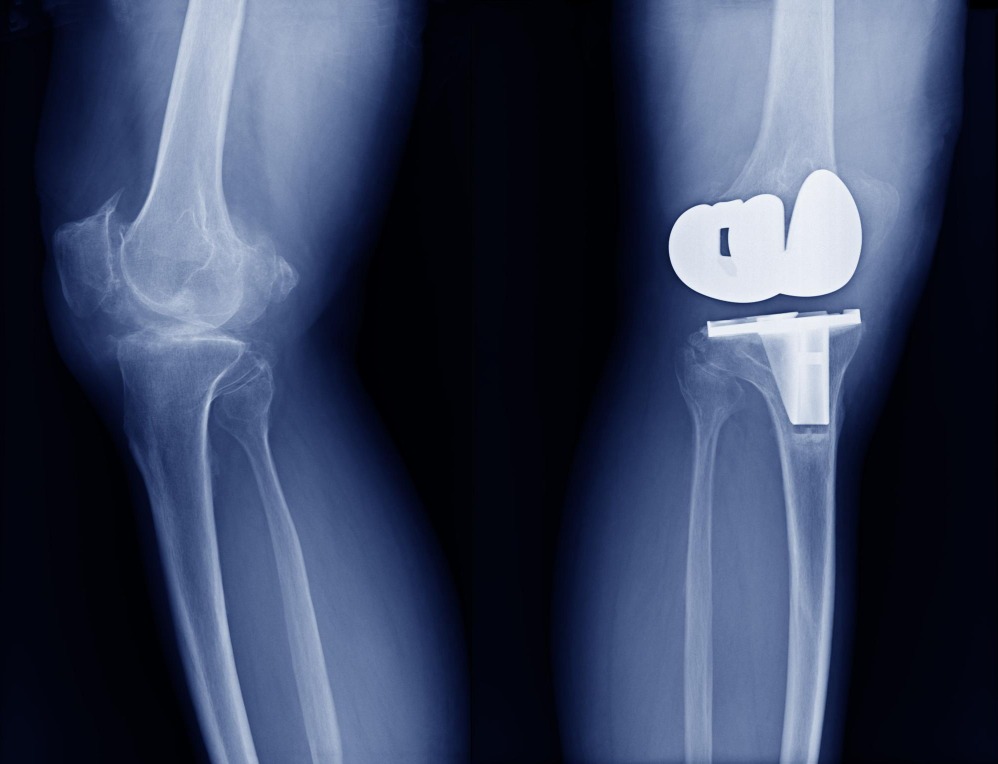

Partial Knee Replacement in Dadar - Targeted Relief for Localised Damage

Knee pain affecting only one area of the joint can feel like a nuisance, but many people don’t realise that this condition can be effectively addressed through partial knee replacement. Dr. Ronak Kothari in Dadar provides expert care to patients who may not need a full knee replacement, focusing on preserving healthy tissue while treating the damaged portion. This approach offers quicker recovery and a more natural feel.

Partial knee replacement is an ideal solution for people who experience localised knee damage due to arthritis or injury. The procedure focuses on replacing only the worn-out part of the knee, keeping the rest of the joint intact. Patients who choose this method often find that they can return to their regular activities faster and with greater comfort.